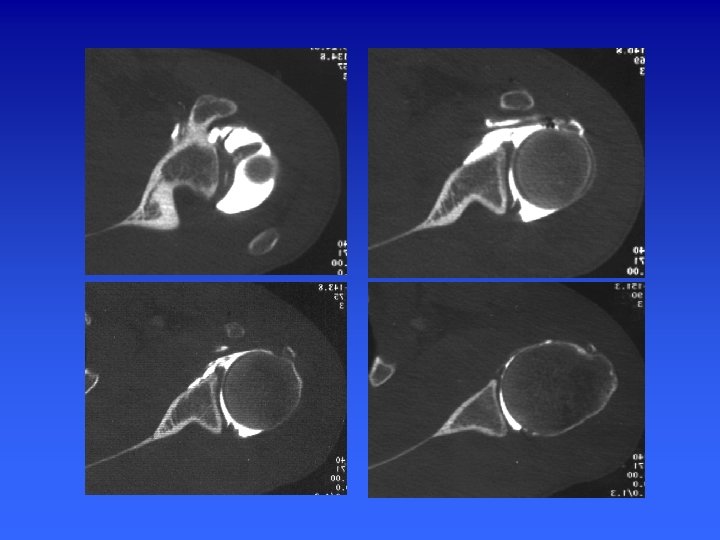

Arthroscanner Indications Actuellement l’examen de référence dans : Les instabilités gléno-humérales La pathologie de la coiffe des rotateurs Cependant il n’explore pas la face superficielle des tendons et ne permet pas le diagnostic des lésions intratendineuses

Arthroscanner 1 er temps : arthrographie classique 2éme temps : acquisition hélicoïdale millimétrique, pitch de 1 à 1, 5 et un incrément de reconstruction de 0, 5 mm. Reconstructions multiplanaires (MPR) sagittales et frontales obliques.

ARTHROSCANNER EPAULE n Positionnement : épaule en position neutre n Topogramme : art acromio-clav - pointe omoplate n Acquisition : hélicoïdale millimétrique de l’articulation acromioclav jusqu’au rebord inf de la glène n Pitch de 1 à 1, 5 et un incrément de reconstruction de 0, 5 mm. W= 2500/600

ARTHROSCANNER EPAULE n Reformatage Axial perpendiculaire à la glène n Para-saggitales dans le plan d’obliquité de la glène n Para-frontal, perpendiculaire au plan de la glène n

Représentation schématique de la coupe d’arthroscanner passant par le pôle supérieur de la tête humérale